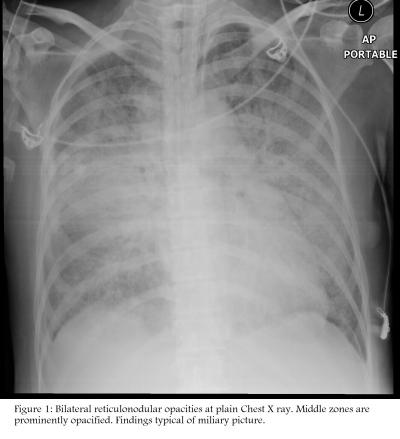

Figure 1: Bilateral reticulonodular opacities at plain chest x-ray. Middle zones are prominently opacified. A typical findings of miliary picture.